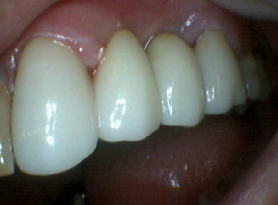

Zirconia Anterior Crowns